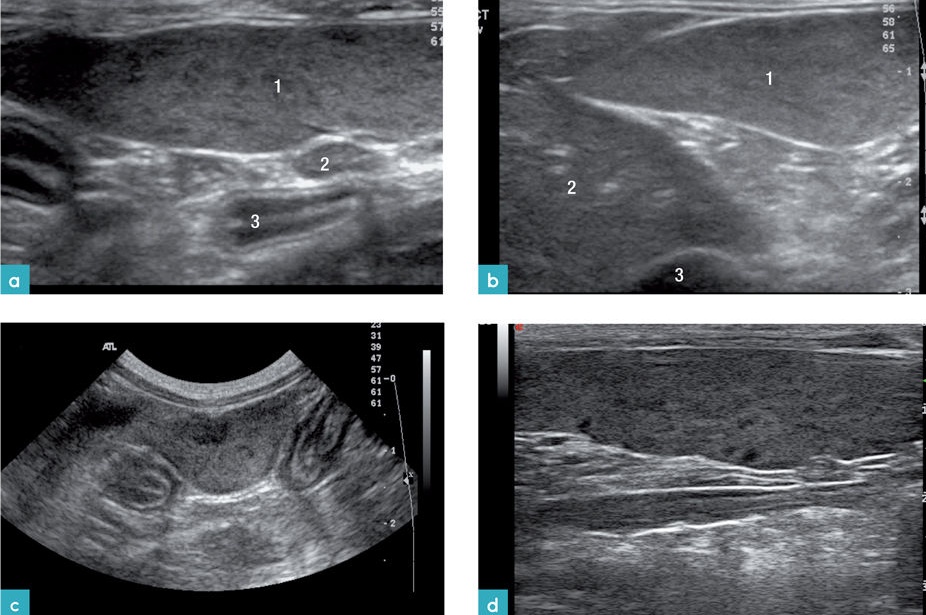

b) convex transducer로 스캔한 비장. 1. 비장, 2. 위의 내강, 3. 위의 추벽

스캔 시 비장의 모양은 혀(tongue) 모양을 가지며, 꼬리부분이 머리 부분과 몸통보다 넓습니다. 횡단면은 삼각형 모양으로 개의 비장보다 작으며, 위치가 일정합니다. 비장의 머리 부분은 위비장 인대에 의해서 위에 고정되어 있으며, 몸통과 꼬리는 많은 유동성이 있으나, 그 유동성의 정도는 개보다 적습니다. 건강한 고양이에서 비장은 얇고, 고에코성의 캡슐표면으로 부드러운 모양으로 잘 확인이 되며, 깨끗한 경계 부위를 가집니다. 비장의 실질은 치밀하고 동질성의 미세한 과립성의 echotexture를 가집니다(그림 2).